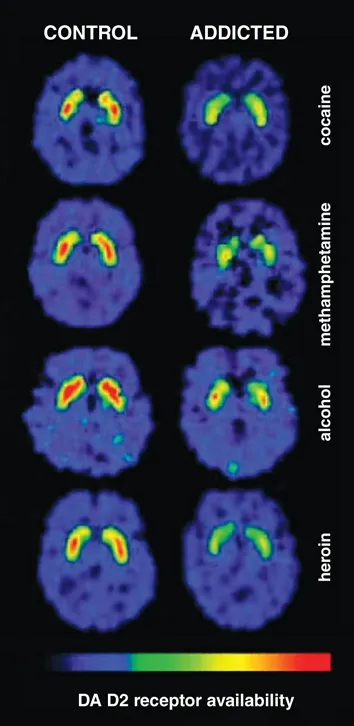

Substance use disorders share a common neurobiological blueprint despite diverse pharmacological profiles. Every addictive substance hijacks the mesolimbic dopamine pathway, creating a 200-400% surge in nucleus accumbens dopamine-far exceeding natural rewards like food (50-100% increase) or sex (100-200%). This fundamental mechanism explains why cocaine, heroin, and alcohol produce similar behavioral patterns despite acting on different primary receptors.